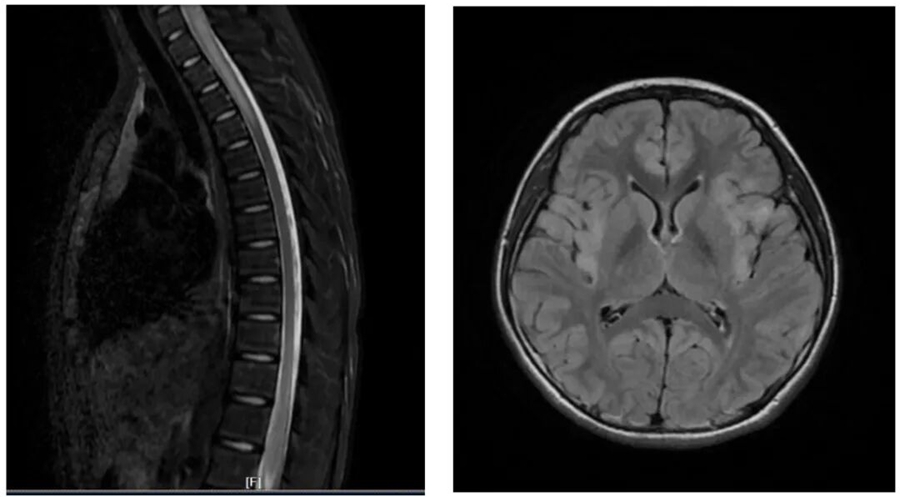

神經內科專家經詳細問診、查體后,當即決定將雙雙收入院,并安排了血液檢查、腰椎穿刺、頭顱 + 全脊髓磁共振等一系列檢查。最終明確診斷,雙雙患有中樞神經系統(tǒng)脫髓鞘病。

這類疾病可分為急性播散性腦脊髓炎、MOG 抗體相關疾病、視神經脊髓炎譜系疾病、多發(fā)性硬化等不同類型。其臨床表現(xiàn)十分復雜多樣,常見的有眼痛、視力下降、癲癇、頭暈頭痛、肢體無力、感覺麻木、二便障礙等,嚴重時還可能出現(xiàn)意識障礙、呼吸衰竭,甚至危及生命,或遺留嚴重的神經系統(tǒng)后遺癥。